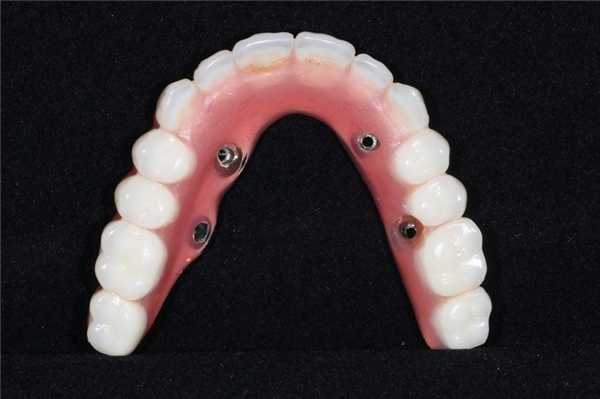

Временный протез функционировал на протяжении 6 месяцев для полной адаптации пациента к внешнему эстетическому виду и новым окклюзионным соотношениям. Окончательная протетическая конструкция состояла из титанового каркаса, покрытого десневым композитом Gradia (GC America), и металлокерамических коронок, зафиксированных поверх титанового базиса (фото 18). Окончательный результат реставрации виден на фото 19.

Фото 18. Вид окончательного протеза через год после первичного вмешательства.